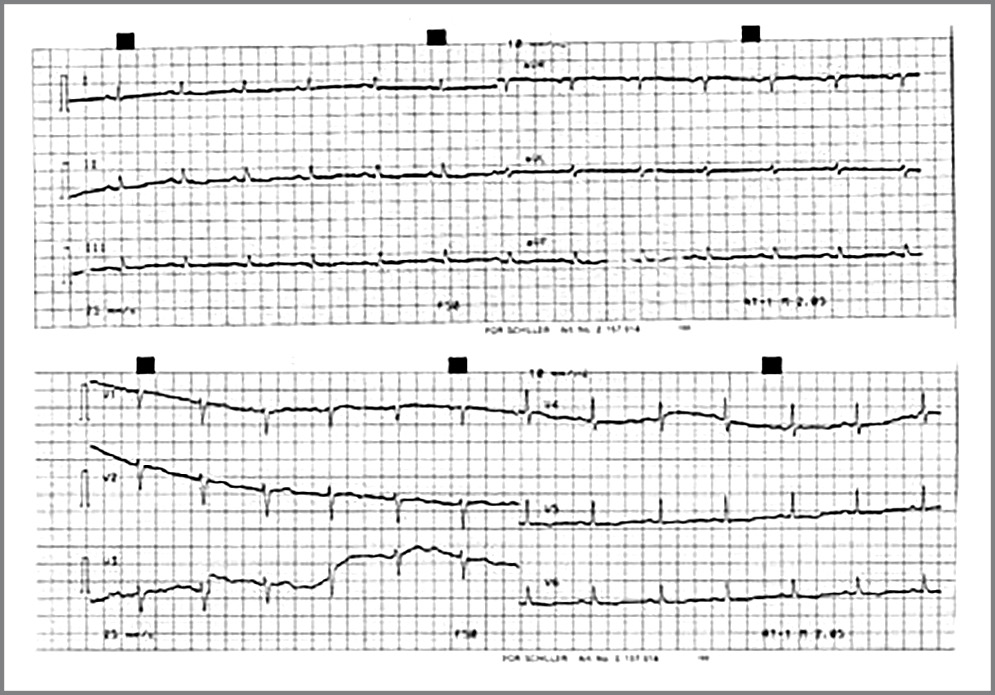

Рентгенография органов ГК. Снижение прозрачности в нижних отделах легких, левосторонний гидроторакс, расширение тени сердца (рис. 3).

Рис. 3. Рентгенограмма органов ГК больной К.

Fig. 3. X-ray of the chest organs of patient K.